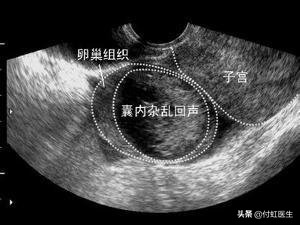

于是,今年付虹医生又加入了体检的大军,这不查不知道,一查吓一跳。妇科盆腔B超发现,我的左侧卵巢上竟然出现了一个2.0×1.6cm的无回声,提示:左侧卵巢囊肿。看来有句戏言什么科得什么病还是有一定道理的。

卵巢囊肿分为生理性囊肿和病理性囊肿。生理囊肿是怎么发生的呢?就是因为在月经的周期中,卵巢在经历卵泡期、排卵和黄体期的过程中出现的囊肿,生理囊肿包括卵泡囊肿、黄体囊肿和卵泡膜黄素化囊肿。

生理囊肿长啥样?特点就是囊肿直径小于6cm,肿瘤标志物也不高,而有生理囊肿的女性也没有什么不舒服,大部分生理囊肿会在1~3个月消失。

卵巢良性肿瘤与恶性肿瘤的鉴别详看下表,从中我们可以看出,恶性肿瘤病程短,迅速增大;肿瘤多为双侧,固定;肿瘤实性或囊实性,表面不平,结节状;患者常有腹腔积液,多为血型,可查到癌细胞。做B超的结果为液性暗区内有杂乱光团、光点,肿块边界不清。